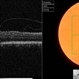

- Severe VMT with 2040 vision

- vitreomacular traction (VMT)

- Imaging device

- Fundus camera

- Colour fundus image of the right eye of an 82-year-old male with 20/40 vision despite severe vitreomacular traction (VMT).